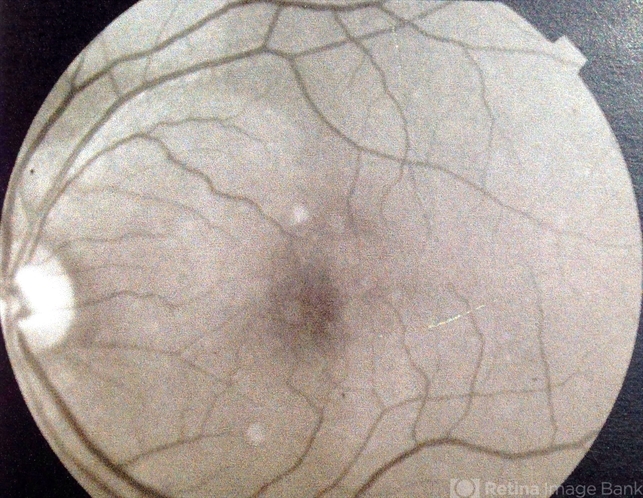

- choroidal hemangioma

- Fundus camera

- Red-free photography reveals a 2 x 3 DD well circumscribed lesion superior nasal to the fovea.